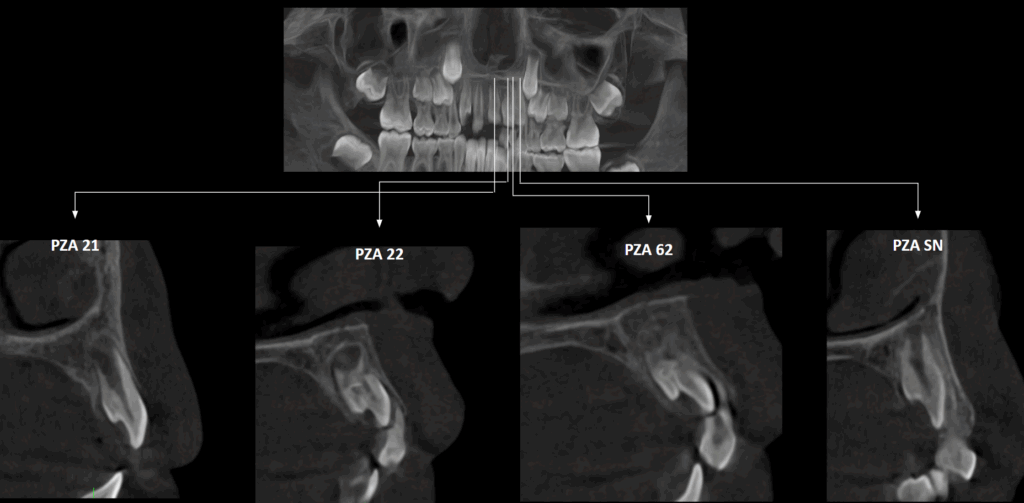

A la evaluación de la tomografía volumétrica (cone beam) bimaxilar en los cortes axiales (Figura 2) y tangenciales (Figura 3) se observa la pieza supernumeraria suplementaria en evolución intraósea (nolla 7) localizada entre piezas 22 y 23 ubicada hacia palatino y en contacto de tercio incisal coronario de pieza 23. Además se observa la pieza 22 en evolución intraósea (nolla 7) con alteración

de la morfología coronaria caracterizada por el repliegue de los tejidos dentarios hacia la cámara pulpar compatible con anomalía dentaria (dens invaginatus).

CORTES TRANSAXIALES